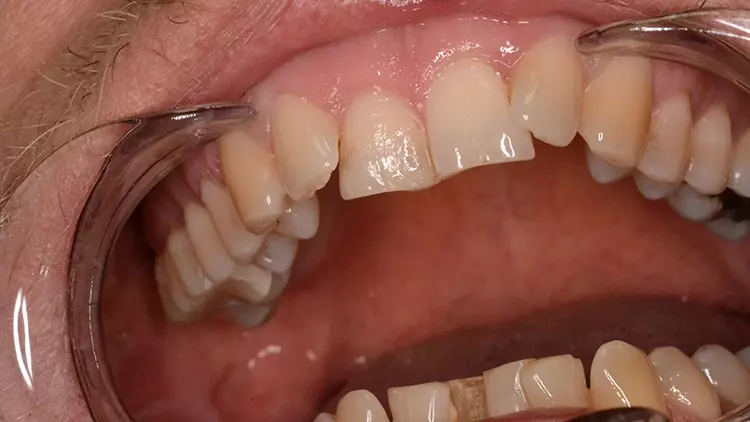

Neugestaltung der Front bei starken Zahnfehlstellungen

Bei dem heute 49-jährigen Patienten wurde seit Kindertagen versäumt, die Ober- und Unterkieferzahnbögen kieferorthopädisch auszurichten. Der Patient leidet seitdem stark unter seinen Zahnfehlstellungen.

Die Fraktur des stark elongierten Zahnes 21 war für den Patienten der Ausgangspunkt, sowohl die Front des Ober- als auch des Unterkiefers prothetisch überarbeiten zu lassen. Dabei wurde der frakturierte Zahn 21 durch ein navigiert eingesetztes Sofortimplantat ersetzt, während die verschachtelt stehenden Zähne 12 und 42 durch eine Brückenversorgung korrigiert wurden (Abb. 4a-j).